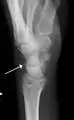

Triquetral fracture indicated by the white arrow.

Triquetral fracture as seen on lateral view of a radiograph.

Triquetral fractures can occur due to forceful flexion of the wrist, causing an avulsion of the dorsal aspect of the bone that is often hidden on anterior radiographs, but can be seen as a tiny bone fragment on lateral views.